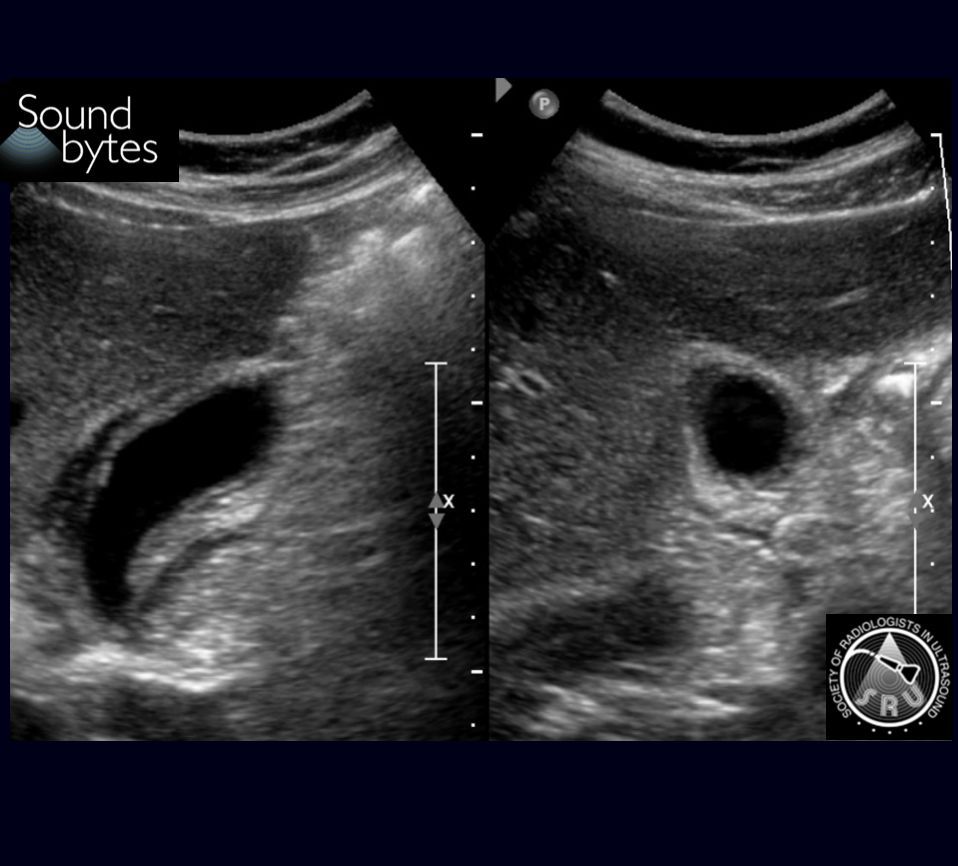

Man with intermittent palpable and painful lump in the groin. What is your sound diagnosis (be specific)?

Case courtesy of Dr. Neel Patel, OHSU

Dx: (Fat containing) *Indirect* Inguinal Hernia

Findings: Herniation of intraabdominal fat between the inferior epigastric and the external iliac vessels.